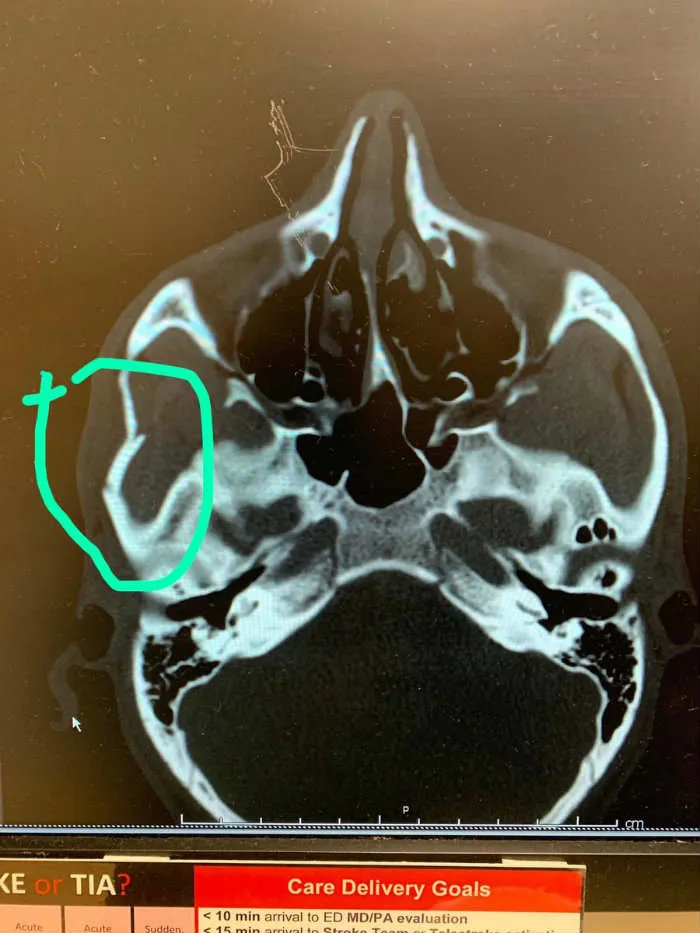

En la búsqueda por un balón, Zlatan aprovechó el impulso y puso el codo en el rostro de su rival, hecho que aún está en espera de determinar si se trata de una fractura en el hueso cigomático, que une al cráneo con el pómulo.